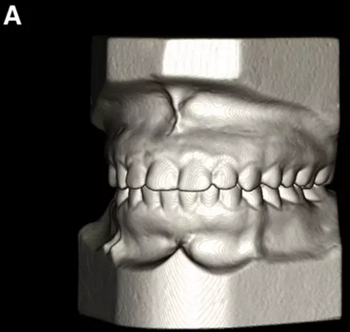

使用體內軟件,第一次融合包括咬合導板在下頜牙齒上定位(圖7)。 圖8顯示了咬合導板和下頜骨(類似咬合導板/游離下頜骨)的完整定位。第二次融合涉及咬合導板的上頜牙齒與顱骨上的的上頜牙齒的定位(圖9)。除了原始的下頜骨最小牙尖分離的3D模型(圖10)之外,這將產生一個構建好的下頜骨完全咬合的3D模型。

圖8. 對游離下頜骨的咬合導板的完整定位。